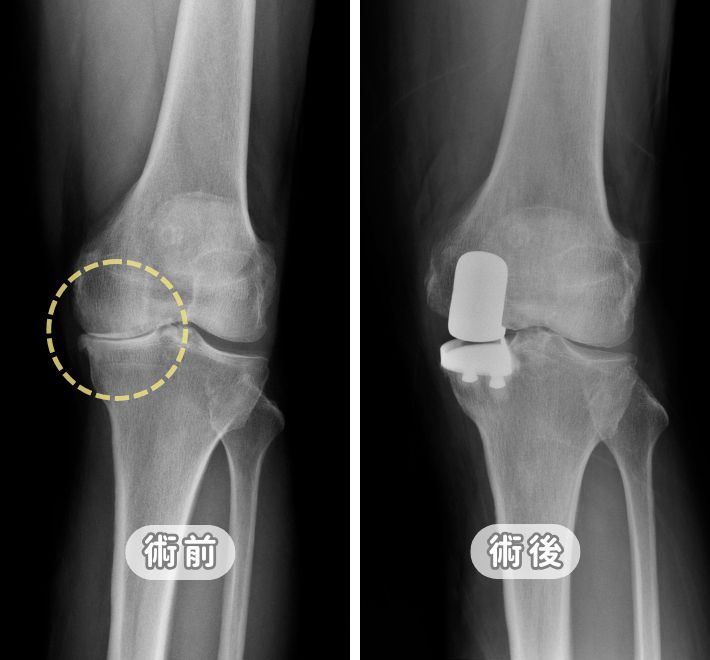

64歲患者的重生案例

一位64歲個案長期受右膝內側疼痛折磨,連走路、爬樓梯都感到困難。經微創關節中心張建鈞醫師詳細評估,其韌帶結構穩定且磨損侷限於內側。

治療方案: 接受新式微創 UKA 手術。

術後表現: 傷口小且出血極少,術後第一天即開始物理治療,兩週後已能自如地穿梭於公園。